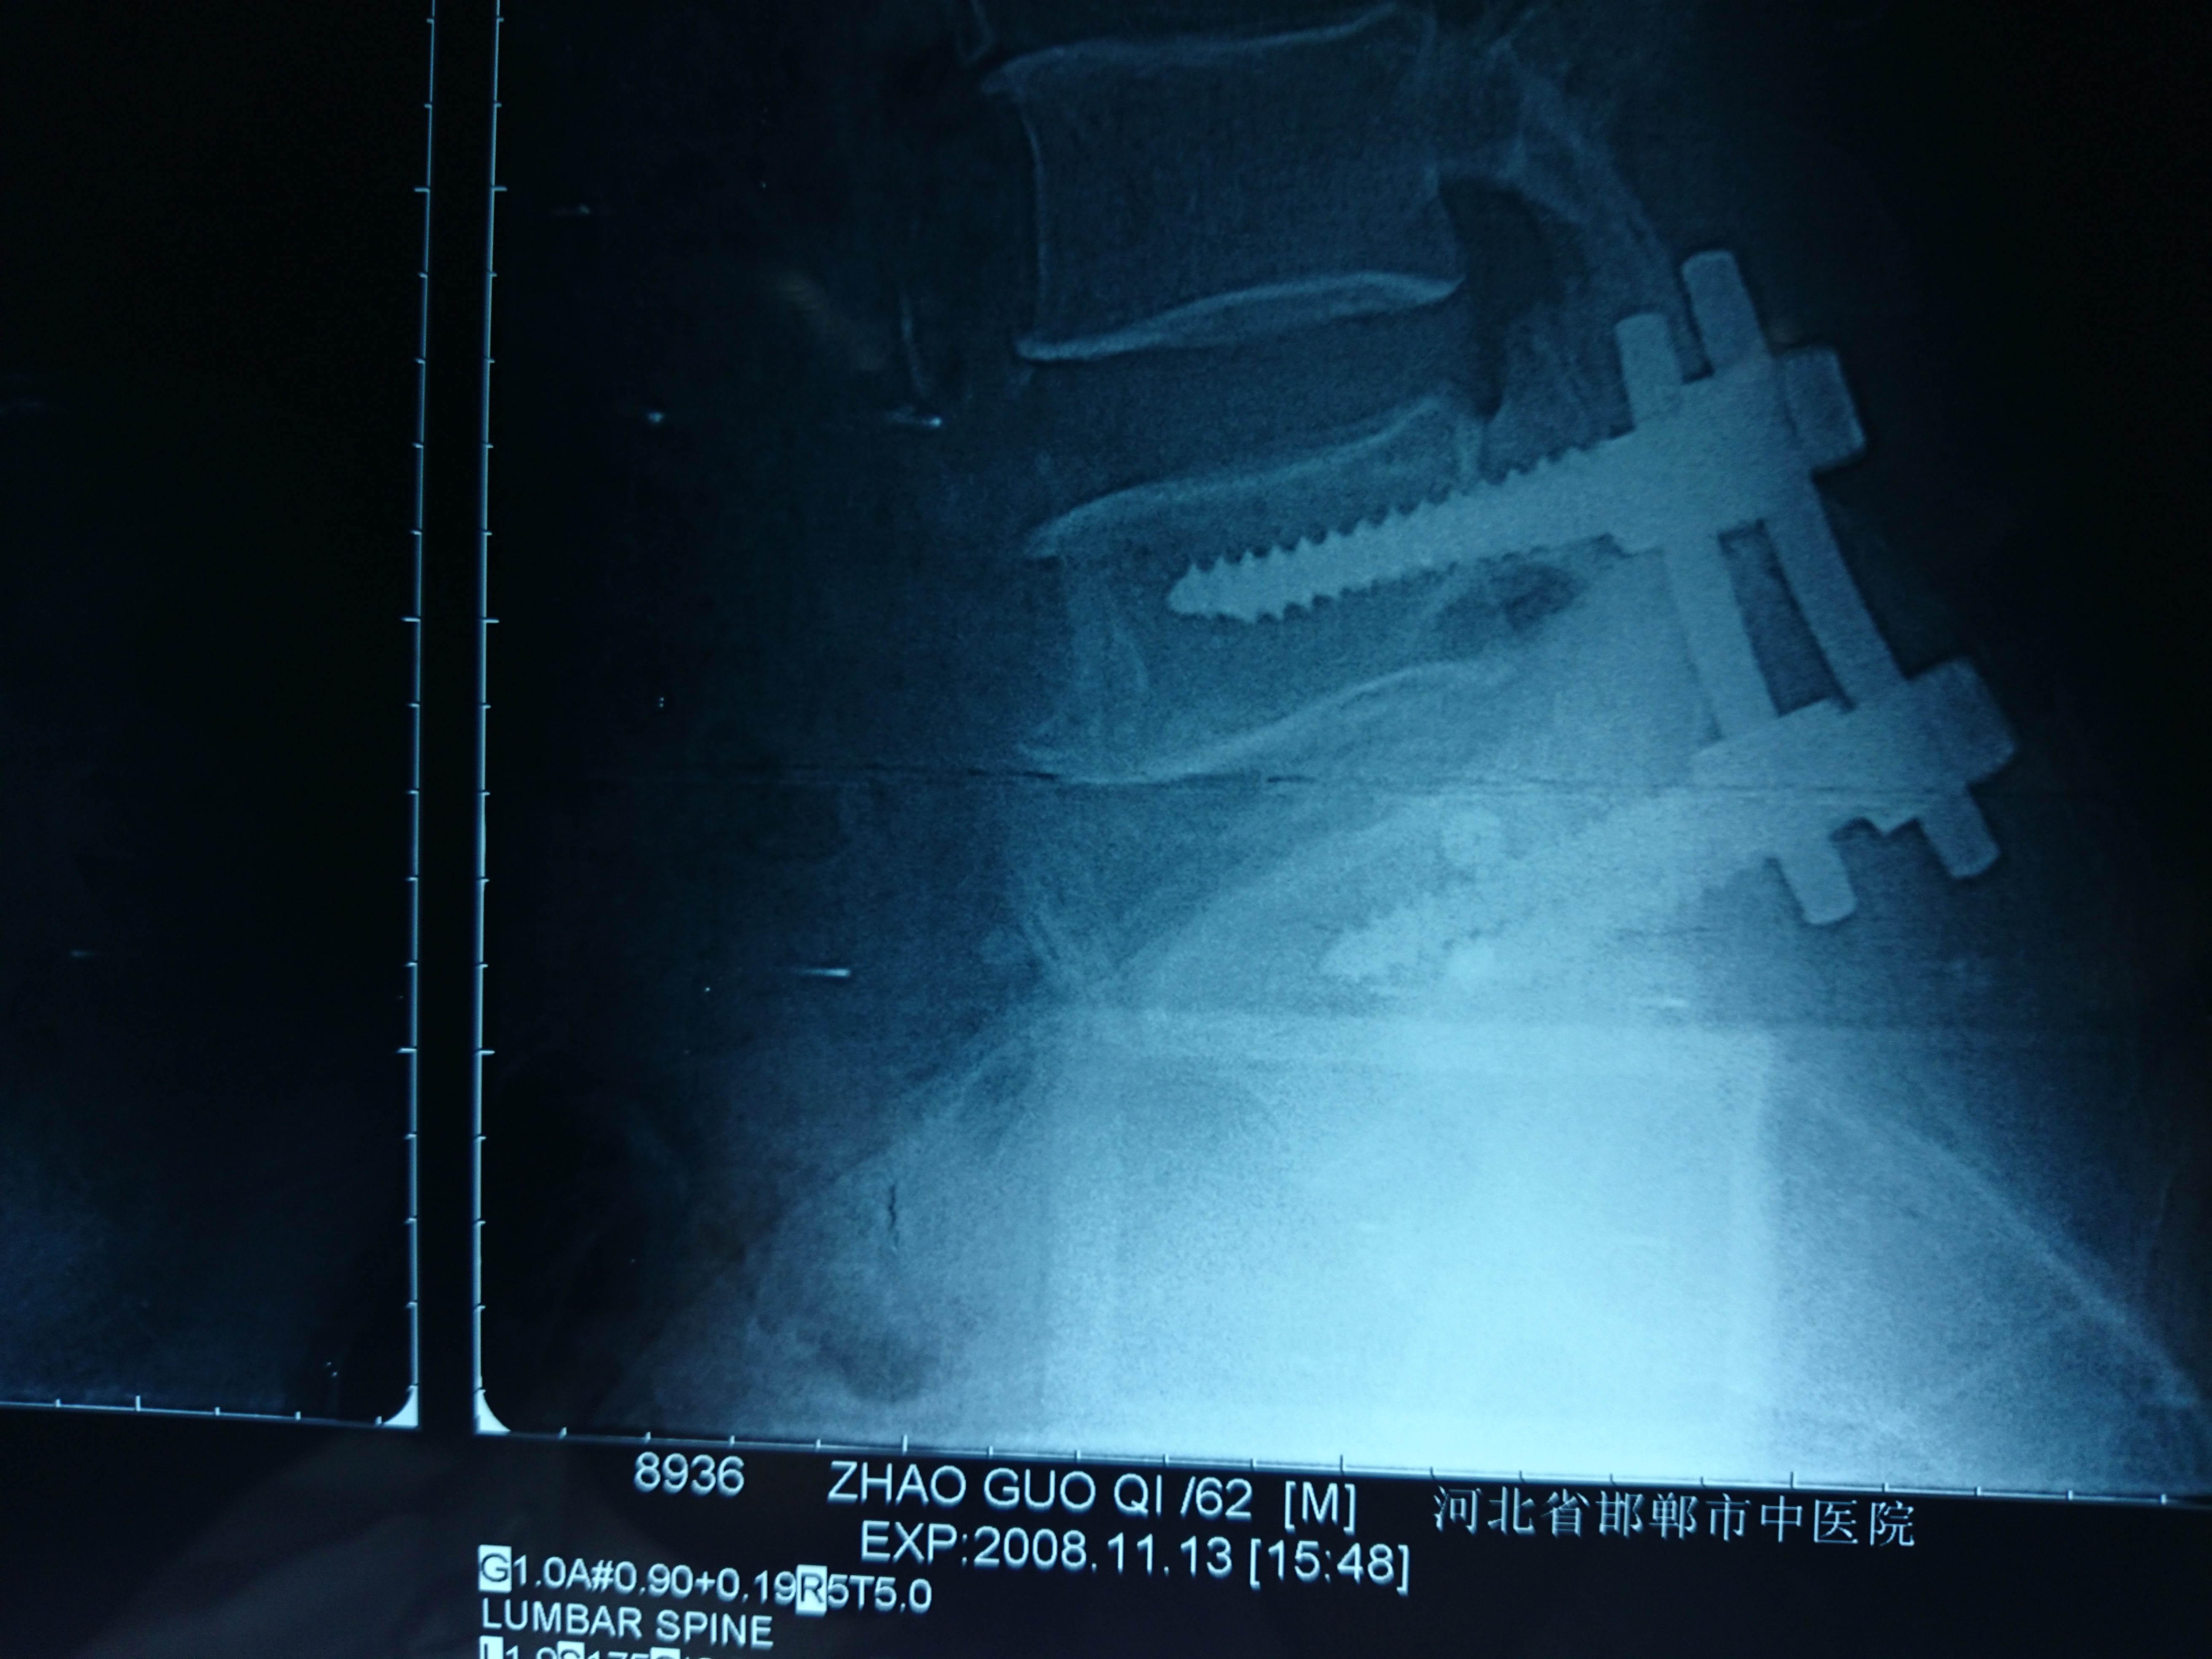

首页 > 张恒云工作室 > 影像资料 三十四